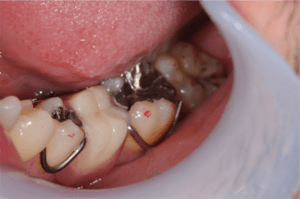

C4虫歯の治療方法

虫歯が歯冠を崩壊して歯肉の下まで進行した場合は、抜歯が必要となります。抜歯後の治療方法は、入れ歯・ブリッジ・インプラントの3つがあります。いずれの場合も、抜歯後歯肉が回復してから処置を開始します。まれにインプラントで抜歯して即時埋入という方法を取る場合がありますが、好条件が整っていないと行えない手技です。

C4状態の虫歯症例の口腔内写真

C4の歯を抜歯後入れ歯をセットした症例の口腔内写真